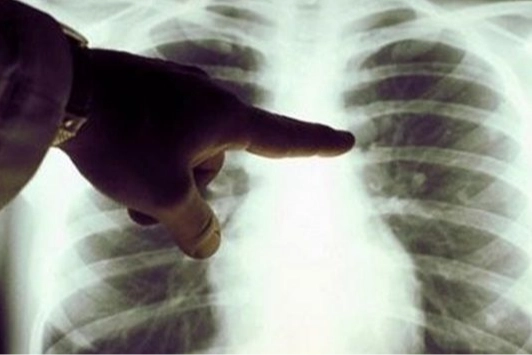

Akciğer kanserine yakalanmamak için bunlara dikkat edin!

Uzm. Dr. Elif Yaldız, “Akciğer kanseri; akciğerlerde anormal hücrelerin kontrolsüz olarak çoğalması sonucunda ortaya çıkar. Kontrolsüz bir şekilde bölünen hasarlı hücreler, sonunda organların düzgün çalışmasını engelleyen doku kitleleri veya tümörleri oluşturur. Akciğer kanseri bölgesel olarak akciğerlerde ilerleyebilir veya lenfatik sistem ya da kan yoluyla diğer doku ve organlara yayılabilir. Akciğer kanseri hem gelişmiş hem de gelişmekte olan ülkeler için önemli bir ölüm nedenidir. Dünya genelinde ve Amerika’da hem erkeklerde hem de kadınlarda kansere bağlı ölümlerin en sık nedeni olup, tüm kanser ölümlerinin kabaca 1/5’inden (.4) sorumludur. Bu sayı her yıl meme, kolon ve prostat kanserinden dolayı kaybedilen hasta sayısı toplamından daha yüksektir. Akciğer kanserleri başlıca iki gruba ayrılır: Küçük hücreli akciğer kanseri (KHAK) ve küçük hücreli dışı akciğer kanseri (KHDAK). Bu sınıflandırma tümörün mikroskobik görüntüsüne dayanarak yapılır. Bu iki tip kanserin büyüme hızları, yayılımları ve tedavileri farklıdır” dedi.

“AKCİĞER KANSERİNİN TANISI NASIL KONULUR?”

Uzm. Dr. Elif Yaldız, “Göğüs hastalıkları bölümüne şikayetle başvuranlarda hekim hastanın tıbbi öyküsünü alır ve sigara kullanımı ve diğer risk faktörlerini sorgular. Yapılan fizik muayenenin ardından akciğer grafisi ile birlikte bazı laboratuvar testleri istenir. Muayene ve akciğer grafisi bulguları ile akciğer kanserinden şüphe edilen hastalarda öncelikle bilgisayarlı tomografi çekilir. Bilgisayarlı tomografi ile elde edilen üç boyutlu görüntü sayesinde hastalıklı bölgeye nasıl ulaşılabileceğine karar verilir. Hastaların çoğunda tanı için akciğerlerden doku parçası alınır. Bu işleme biyopsi adı verilir. Biyopsiler çeşitli yöntemler ile yapılabilir. Bazı durumlarda deriyi geçip akciğer içine doğru bir iğne ilerletilebilir ki bu ‘’iğne biyopsisi’’ olarak adlandırılır. Bazen de biyopsi ‘’bronkoskopi’’ adı verilen işlem ile elde edilir. Bu işlemde ince ve ucunda bir ışık bulunan bir hortum kullanılarak akciğerin havayolları incelenir ve küçük doku parçaları alınır. Akciğer etrafındaki zarda sıvı birikimi olmuşsa buradan iğne biyopsileri alınabilir (torasentez, plevra biyopsisi). Bir diğer yöntem de dokuların cerrahi yöntemlerle alınmasıdır (mediastinoskopi, video eşliğinde torakoskopik cerrahi, açık akciğer biyopsisi). Alınan bu doku parçalarının bir patolog tarafından incelenmesi oldukça önemlidir. Çünkü akciğer kanseri hücre tipinin kesin olarak bilinmesi tedaviye yön veren en önemli bilgidir. Yapılan diğer testler genellikle kanserin vücuttaki yayılımı hakkında bilgi sahibi olmak için yapılır. Bu testler ise hastanın şikayetlerine göre manyetik rezonans görüntüleme (MR), kemik sintigrafisi, ultrasonografi veya PET-BT (pozitron emisyon tomografi) olabilir” dedi.